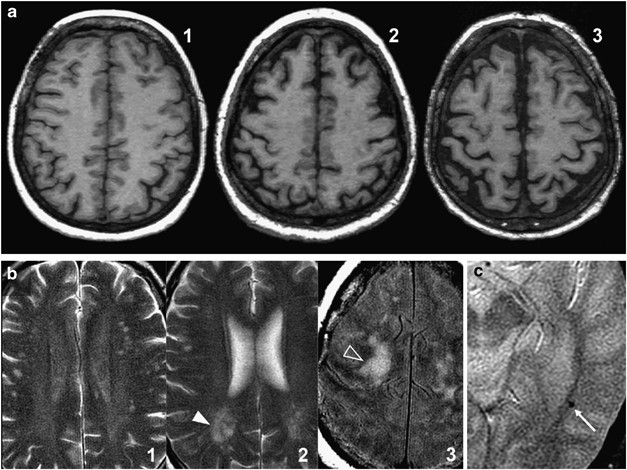

Figure 1

(a) Atrophy scoring. Axial reformatted 3-mm thickness T1-weighted images. From left to right are images from three different patients showing no atrophy (1), some atrophy (2) and substantial atrophy (3). No patient in our sample met the criteria for end-stage atrophy. (b) Ischemia scoring. Axial long TR double-echo images. From left to right are images from three different patients with punctate lesions (1), beginning confluent lesions (2, white arrowhead) and confluent lesions (3, open arrowhead). (c). Microbleeds. Axial gradient-echo T2-weighted image. Tiny hypointense brain lesion (arrow) corresponding to a small hemorrhage.